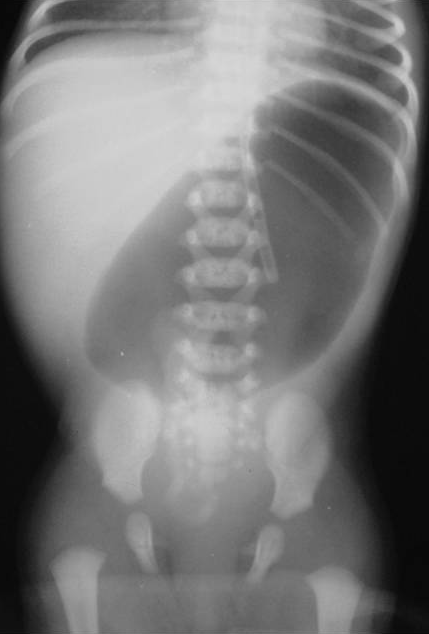

En neonatos, la obstrucción intestinal puede ser diagnosticada mediante una serie de hallazgos radiológicos característicos. La evaluación radiológica es crucial para diferenciar entre las diversas causas de obstrucción intestinal, que pueden ser de origen alto o bajo, y para determinar el manejo adecuado.

1. Radiografía Abdominal: Es la primera línea de imagen utilizada para evaluar la obstrucción intestinal en neonatos. Los hallazgos típicos incluyen dilatación de asas intestinales y la presencia o ausencia de niveles hidroaéreos, lo cual puede indicar si la obstrucción es proximal o distal. Por ejemplo, la «burbuja única» se asocia con atresia esofágica, la «doble burbuja» con atresia duodenal, y la «triple burbuja» con atresia yeyunal.[1-2]